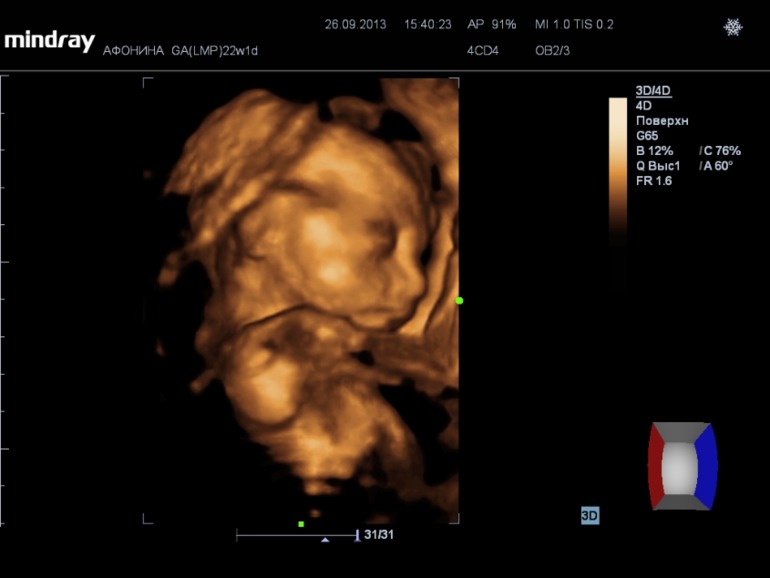

На 3d нам сказали что ребеночек ну очень щекастый, нос картошкой))) Наделали кучу фото и видео (запись на диск 300р), насмотрелись вдоволь. А в самом конце нам сказали пол.....

у нас будет девочка!!!!!!!!!!!!!!!!!!!!!

А вот и фото нашей принцессы))) (под кат)